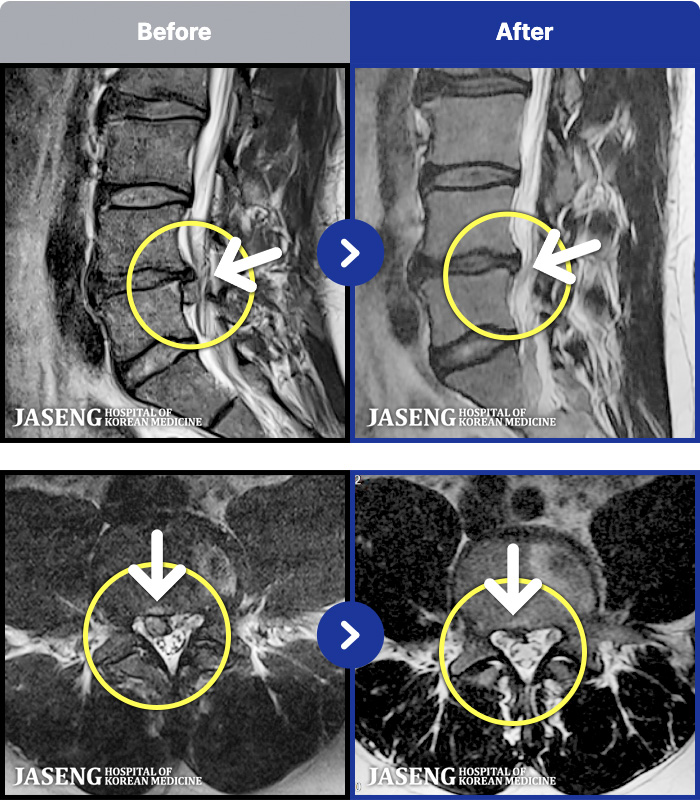

MRI ġ

MRI ũ ʸ Ȯϼ.

Ƹ ϰ ־.

ǿ

õ

ȯ

㸮ũ

¥

2025.08.01

ȸ

14,435

[õ] 25.03.18~25.07.22

ȯںп Ǹ ǿ ԿǾ, ο ġ ۿ Ƿ ġḦ Ͻñ ٶϴ.